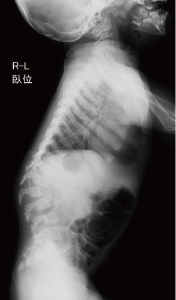

C. 脊椎側面像(2歳、女):椎体前縁が後縁より高い扁平椎が乳幼児期には特徴的である。